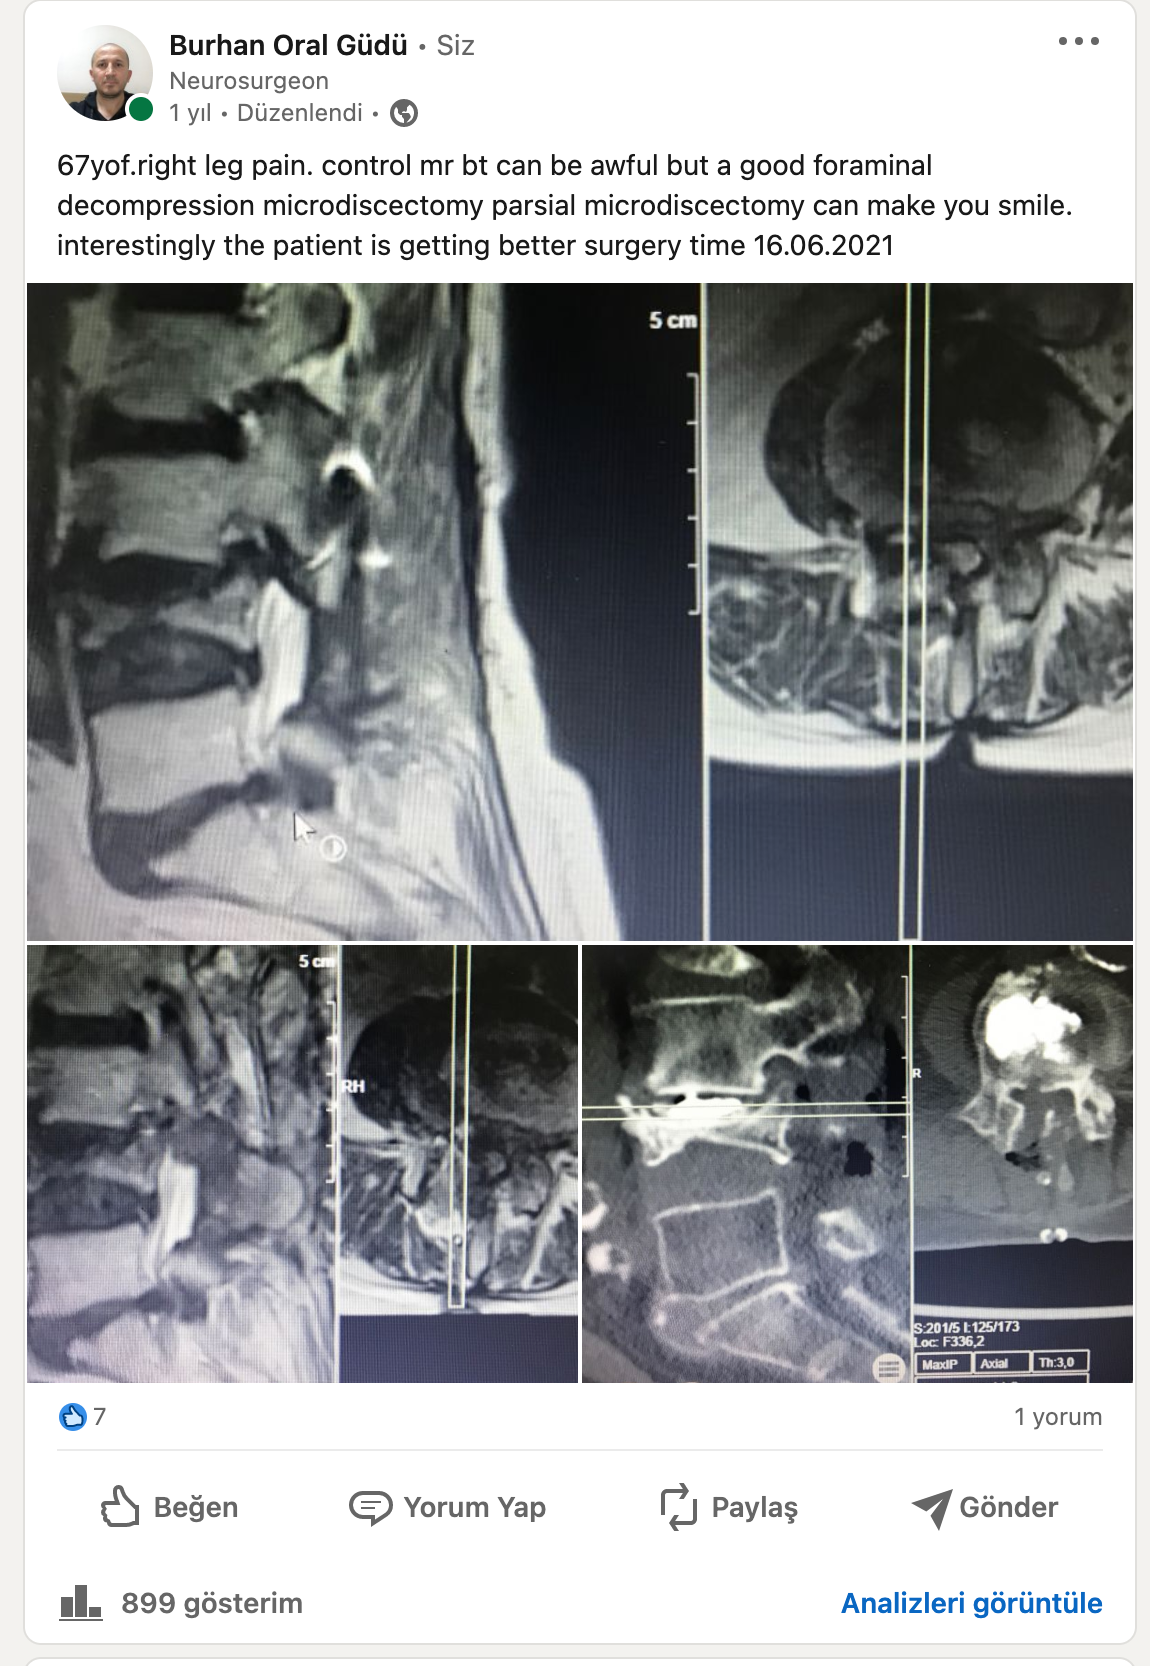

Siyatik